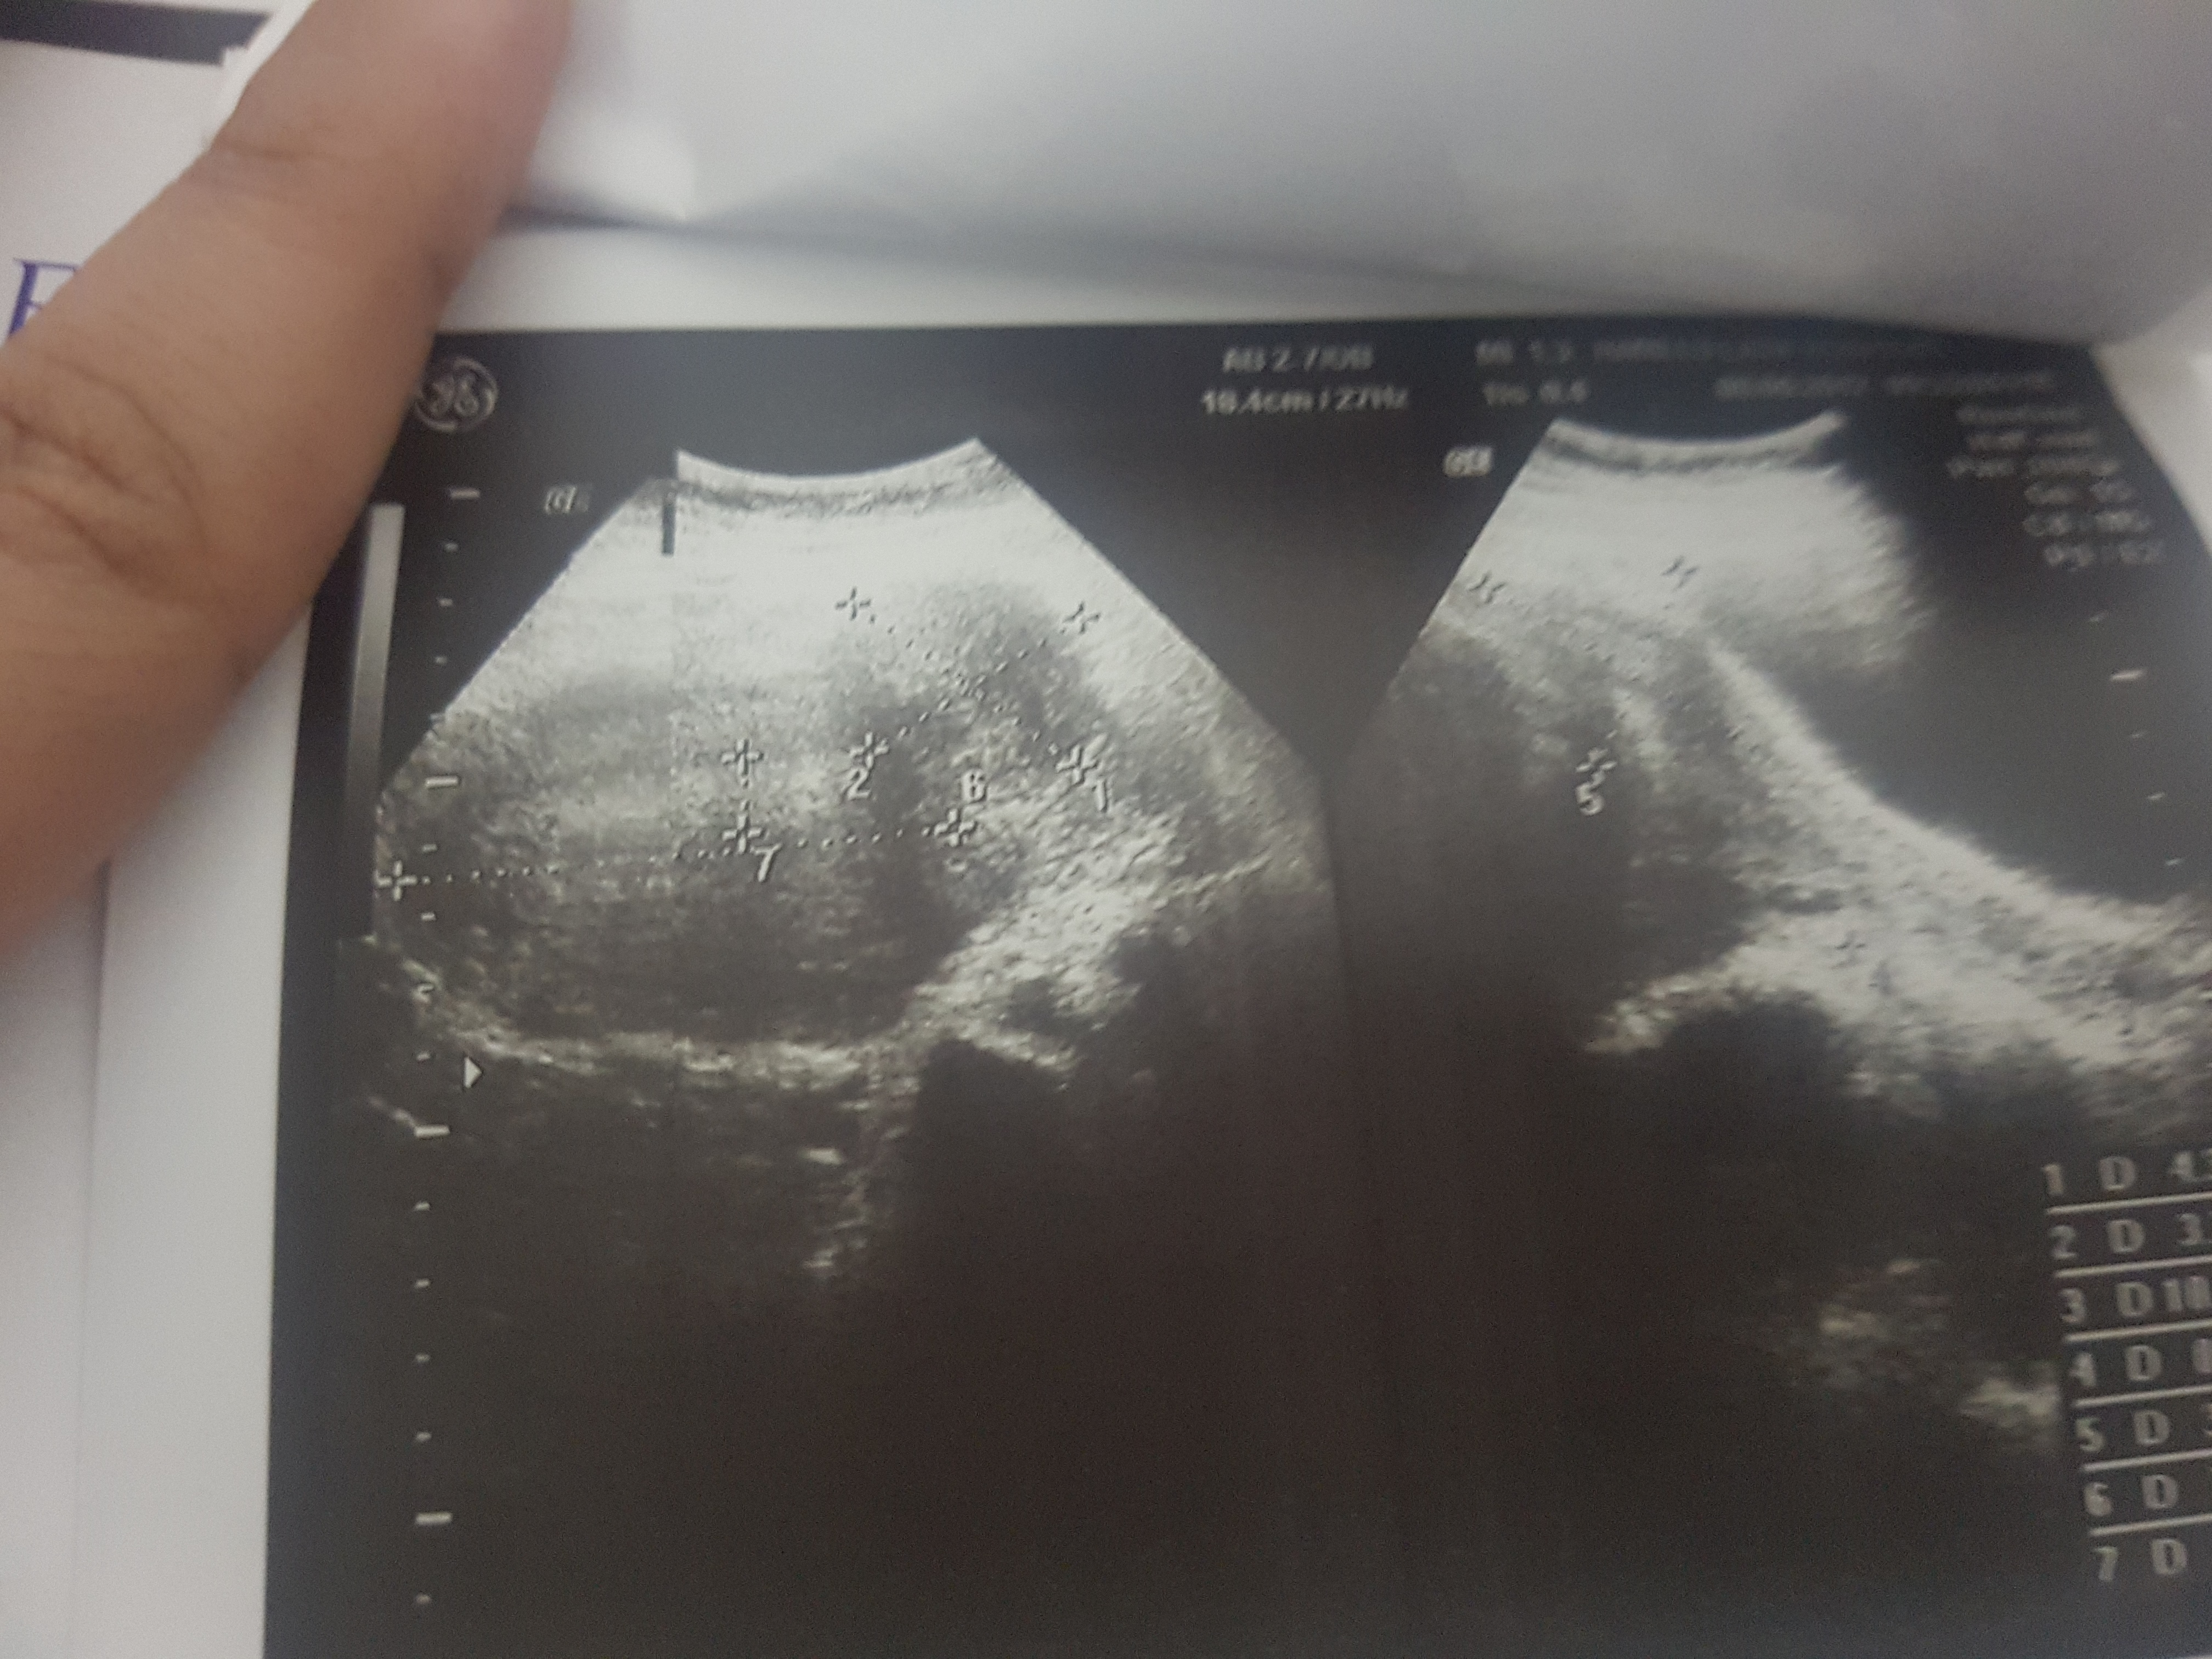

these r my ultrasound report should i go for surgery?? ak br mai ny expect kia ha par result was explusion in 24 weeks plzz guide me im not conceiving again

ak dafa mai ny conceive kia tha 24 weeks mai explusion 6 mnths phly hwa tha us k bd abi tk concieve nai says k take 1 more chance.. surgery k bd conpliction hti ha conceive krny mai